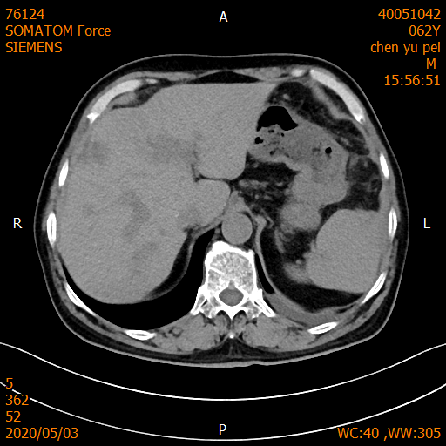

2020-05-03 增强CT示胸部+全腹部增强CT:1、结肠癌术后:左侧腹造瘘改变,左上腹网膜增厚,请结合临床;2、肝脏多发转移,较前缩小。

该患者经西妥昔单抗联合化疗治疗后,患者临床症状好转。肿瘤标志物如:CEA、CA19-9、CA72-4、CA24-2均逐步下降中。影像学检查提示肝脏转移病灶较前缩小,未出现新的转移病灶。考虑治疗有效。